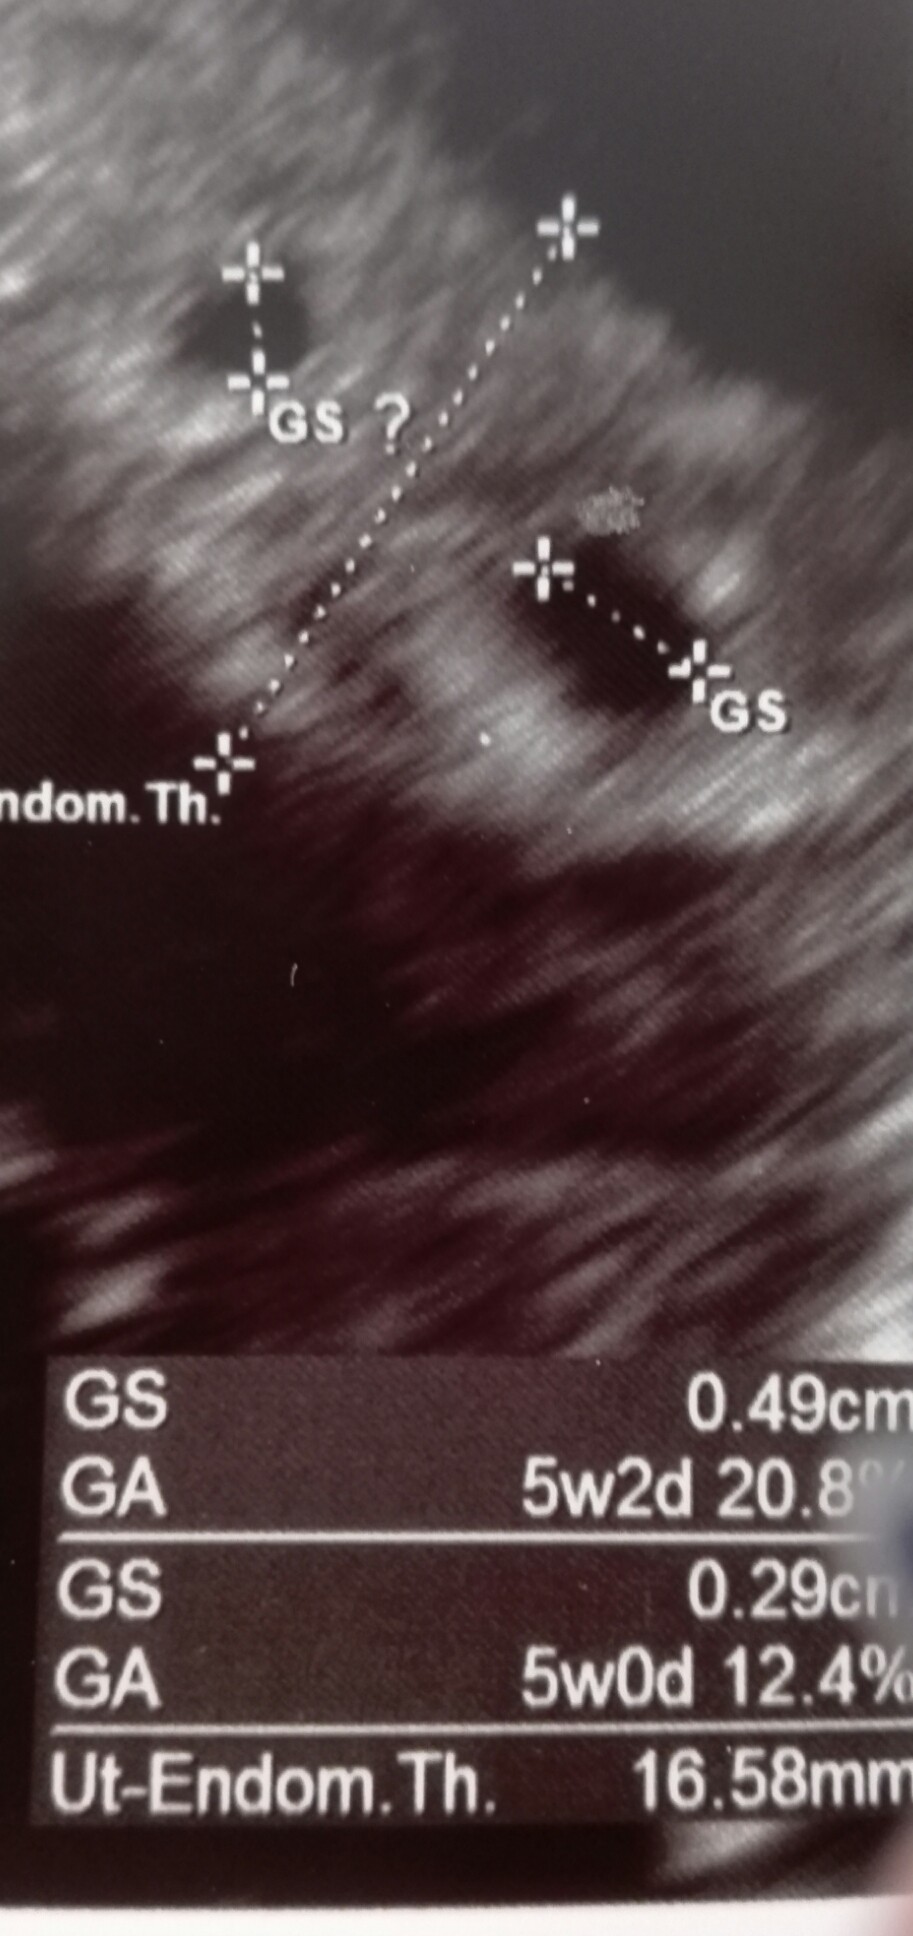

Wpisuję się chwilowo w ten wątek (mam nadzieję, że na dłużej) i postanowiłam przyłączyć się do dyskusji. Wczoraj miałam 1 USG (to 3 ciąża, pozostała dwojka ma już 3.5 i 8.5 lat), 5 tydzień, 2 pęcherzyki, ale nierówne. 2 dni niby tylko między nimi, ale lekarz kazał się do myśli o bliźniakach nie przyzwyczajać. Ta ciąża to była niespodzianka, ale nie zmienia to faktu, że obu groszkom kibicuję. Jak u Was wyszły wczesne USG?

U nas nie widać nic na razie poza pęcherzykami.. a ja szaleję z niepewność i obawy o maluchy...

U mnie w chyba równo 5 tyg Maluchy miały po 0.72 i 0.82 cm, czyli spora różnica, a zostały oba[emoji7] Nie martw się na zapas. Owszem zdarzają się przypadki, że gdzieś po drodze jedna Kropeczka znika, ale nikt nie powiedział, ze tak będzie u Ciebie. Trzymam kciuki[emoji7] [emoji7]